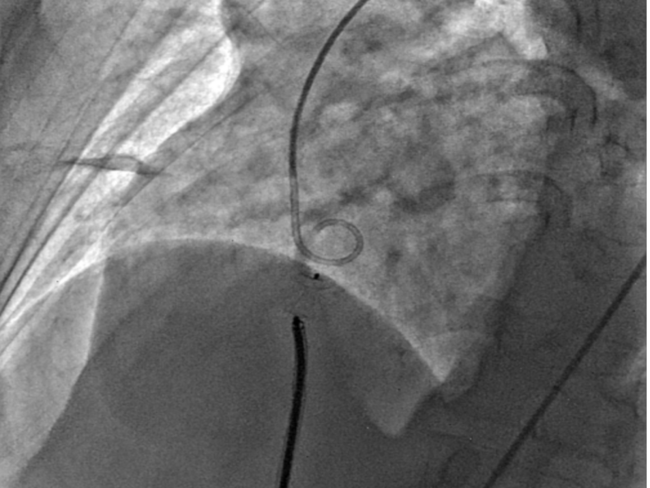

A 7 French delivery sheath was traversed across the ruptured sinus, through the inferior vena cava, to the aorta (Figure 3, Video 3).

Figure 3. Advancement of a 7 French (F) sheath (green arrow) across the arteriovenous (AV) rail.